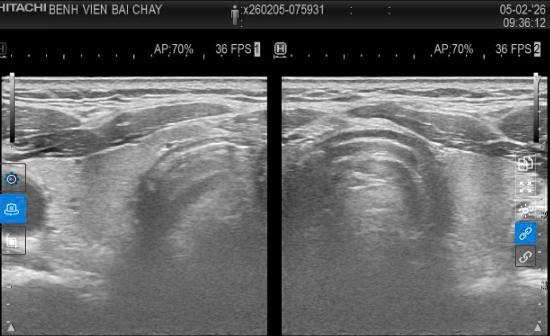

Kết quả tái khám và theo dõi sau điều trị cho thấy khối u đã được phá hủy hoàn toàn, không còn dấu hiệu tổn thương ác tính, chức năng tuyến giáp được bảo tồn tốt, sức khỏe bệnh nhân ổn định.

Hình ảnh siêu âm sau can thiệp một năm rưỡi, khối u mất hoàn toàn.